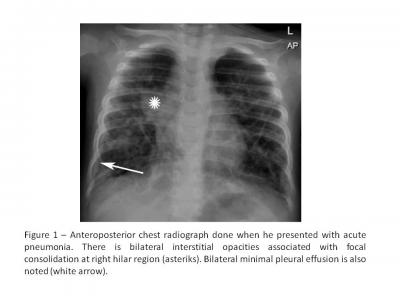

Figure 1: Anteroposterior chest radiograph done when he presented with acute pneumonia. There is bilateral interstitial opacities associated with focal consolidation at right  hilar region (*). Bilateral minimal pleural effusion is also noted (white arrow)